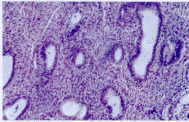

2.2 子宫内膜组织学 根据Noyes标准, 实验组中与月经周期同步者2例, 分泌不足或延迟11例,其中延迟2~3天的7例、 延迟1天的1例。延迟4天3例:分泌与增生混合存在的7例, 均是部分腺体为增生改变而间质细胞出现分泌改变。对照组10例中除1例分泌延迟1天外,其余均与月经周期同步。实验组腺体较稀疏,小腺体所占的比例较大(见图1,2)。

图1 服克罗米芬排卵后第8天,分泌延迟3天,腺体发育差,小腺体较多,间质分泌反应差.×100

图2 服克罗米芬排卵后第8天,腺体分泌与增生改变混合在.×200